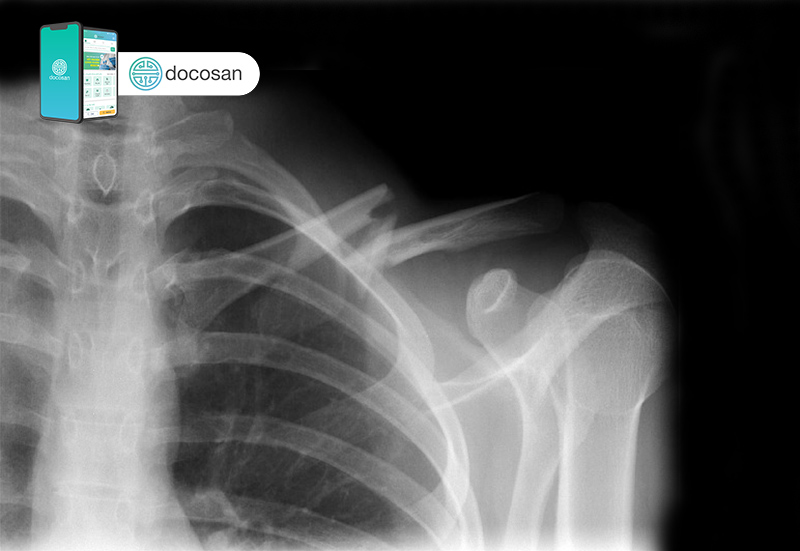

Bác sĩ sẽ cần làm thêm một số cận lâm sàng để đảm bảo rằng không có tổn thương thần kinh hay mạch máu kèm theo. X-quang là công cụ hình ảnh học đầu tiên được tiếp cận. X-quang xương đòn giúp xác định vị trí và mức độ của gãy xương. Có thể cần chụp thêm phim x-quang các xương khác của vùng vai. Nếu có kèm gãy xương khác, có thể bạn sẽ cần chụp cắt lớp vi tính (CT scan) để chấn thương được đánh giá chính xác hơn.